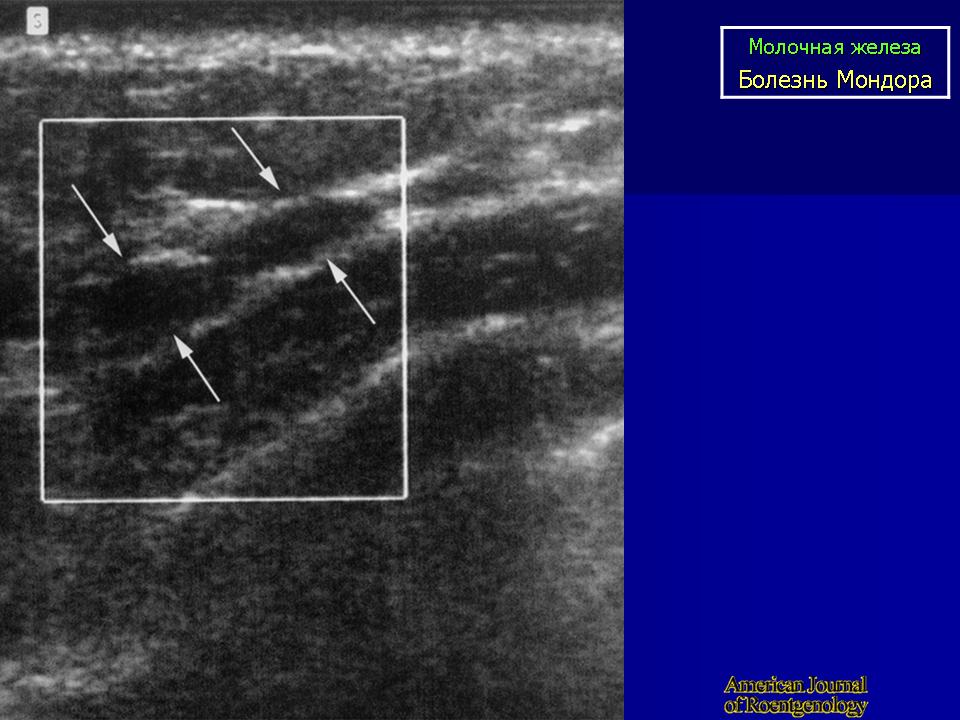

БОЛЕЗНЬ МОНДОРА

При болезни Мондора у больных по ходу сосудов на грудной и брюшной стенке в области молочной железы возникают болезненные, шнуровидные утолщения, иногда протяженностью до 20 см.

Температура тела повышается до субфебрильной. В этот период болезни в венах можно найти тромб, вена расширена, стенки её утолщены. Во второй фазе болезни, которая наступает через 10-14 дней после начала, вена подвергается склерозированию. Кожа, в силу близости к вене и отсутствия между ними фасциальных прослоек вовлекается в воспалительный процесс. Поэтому, при натяжении кожи, особенно при поднятии руки, отведении возникают лучеобразные морщинки по ходу вен.

Болезнь Мондора (Morbus Mondor)

Описана автором в 1939 г и известна также, как string phlebitis. Представляет собой воспалительный процесс, охватывающий v. thoracoepigastrica или v. thoracica lateralis, реже v. epygastrca superficialis по передне-боковой поверхности грудной клетки. В целом патогенез заболевания не выяснен. Некоторые авторы связывали возникновение данной формы тромбофлебита с mastitis vestigial. Существуют предположения об инфекционной и вирусной природе болезни Мондора, поскольку в ряде случаев отмечается увеличение регионарных лимфатических узлов. Встречается преимущественно у женщин среднего возраста, особенно с большими размерами молочной железы и иногда сопутствует неопластическому процессу в последней. В отдельных случаях пальпаторная характеристика тромбированной вены по своей твердости напоминает хорду, что дало основание для еще одного наименования: cord-like phlebitis. Температурная реакция чаще всего отсутствует. Рецидивы практически не наблюдаются. Морфологически обнаруживается облитерирующий эндофлебит.